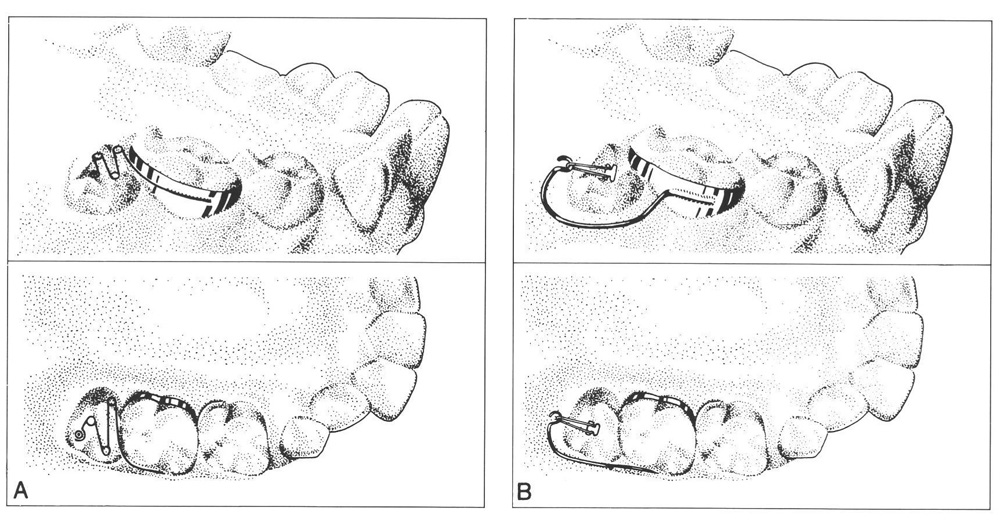

16 Problems in Eruption of First and Second Permanent Molars Pocket Brass Wire Ectopic Eruption Ectopic eruption (ee) is defined as a localized disturbance in the eruption path of a tooth leading to an abnormal position or orientation of that tooth. Ee of permanent first molars is observed when the molar assumes an abnormal mesioangular path of eruption, resulting in an impaction at the distal aspect of the primary second molar. If left untreated, many. Brass Wire Ectopic Eruption.

Halterman technique for the treatment of ectopically erupting permane… Brass Wire Ectopic Eruption Sert the distorted brass wire can cause soft tissue damage. Ectopic eruption of permanent molars is one of the challenges that arise in the early mixed dentition period, particularly when the root of the primary. Ee of permanent first molars is observed when the molar assumes an abnormal mesioangular path of eruption, resulting in an impaction at the distal aspect. Brass Wire Ectopic Eruption.

Halterman technique for the treatment of ectopically erupting permane… Brass Wire Ectopic Eruption Ee of permanent first molars is observed when the molar assumes an abnormal mesioangular path of eruption, resulting in an impaction at the distal aspect of the primary second molar. Ectopic eruption of pmfm is a common eruption disorder occurring during mixed dentition. Ectopic eruption of permanent molars is one of the challenges that arise in the early mixed dentition. Brass Wire Ectopic Eruption.